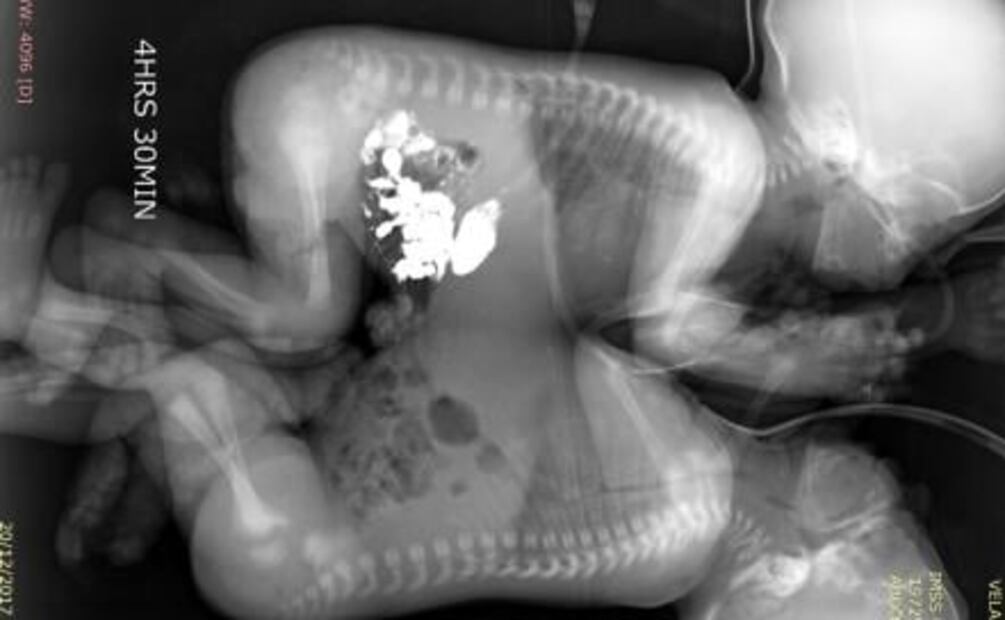

Después del alumbramiento, los menores de edad fueron sometidos a exámenes de tomografía, ecocardiograma y resonancia magnética, cuando cumplieron 41 días de vida, se decidió programar la cirugía que los separaría.

La intervención quirúrgica se realizó por un equipo multidisciplinario de cirujanos, anestesistas y grupo de enfermería , comenzó a las 9:00 horas; de manera cuidadosa ejecutaron la incisión en la línea media que unía a los gemelos y mediante la técnica de electrocoagulación , lograron separarlos a las 12:43 horas, sin que se presentaran complicaciones.